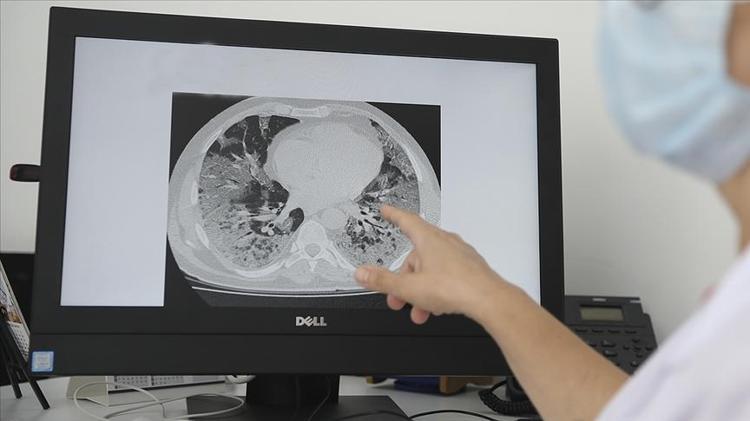

CİDDİ HASTALIKLARA İŞARET EDEBİLİR

Uzm. Dr. Ercan, dikkat edilmesi gerekenler hakkında şunları söyledi:

"Zatürre benzeri belirtiler akciğer kanseri gibi ciddi hastalıklara işaret edebilir. Şüpheli durumlarda göğüs hastalıkları uzmanına başvurulmalıdır. Sağlığımız için erken teşhis ve doğru tedavi büyük önem taşır."